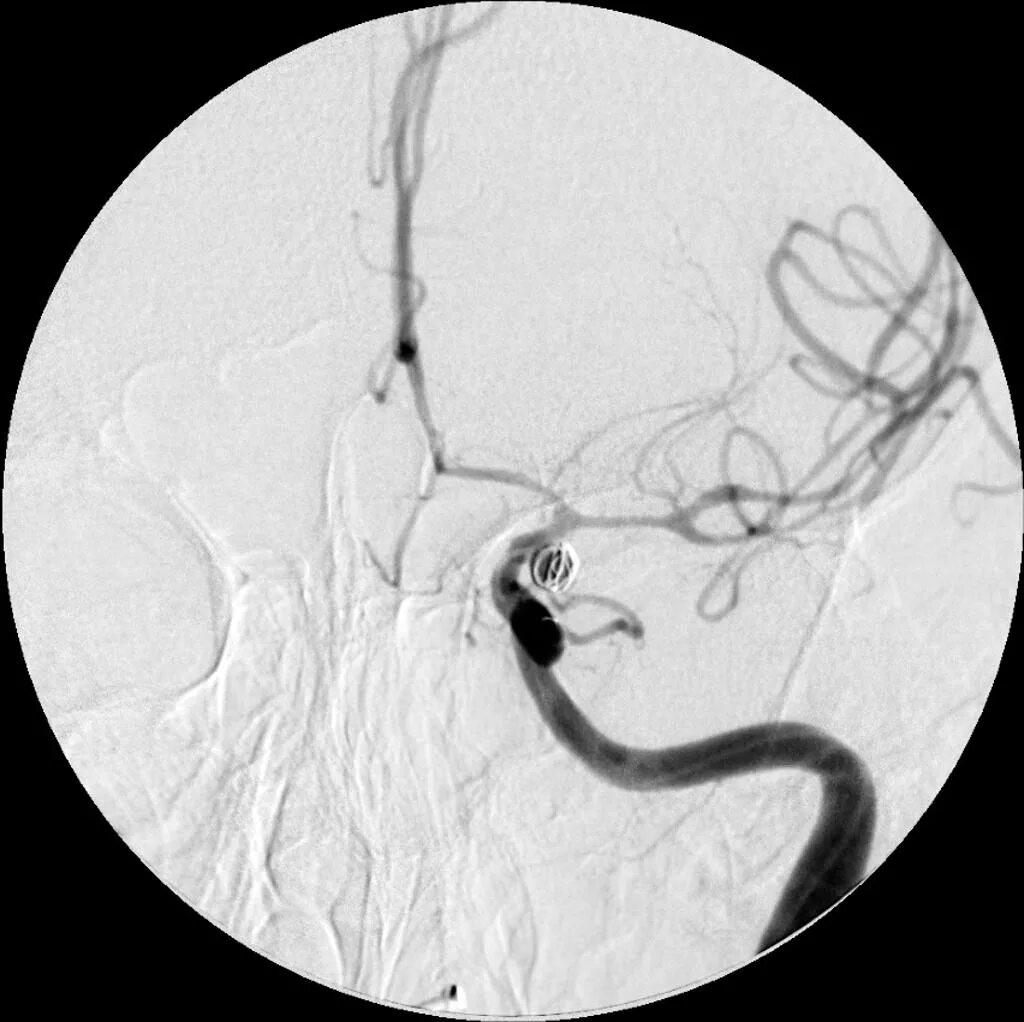

Стеноз спазм